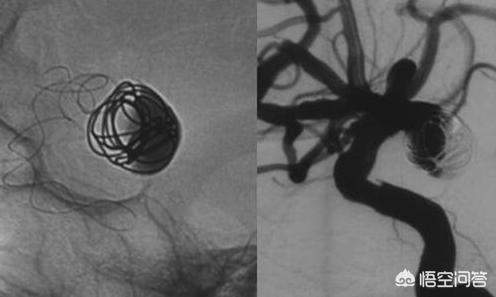

En effet, les vaisseaux cardiaques eux-mêmes ne sont pas visualisés lors de la coronarographie, car il s'agit de tissus mous et les rayons X sont rarement absorbés lorsqu'ils pénètrent, ce qui rend difficile l'obtention d'une image de ces vaisseaux.

Mais tout comme nous pouvons ajouter de l'encre à un courant d'eau claire pour le rendre plus visible, nous pouvons "colorer" le sang (augmenter l'absorption des rayons X) à l'aide d'un produit de contraste.

L'iopromide (Uvixan), l'iodohexol (Onepac), l'iodixanol (Vivipac) sont les agents de contraste les plus couramment utilisés. L'un d'entre eux est injecté dans le corps pendant l'imagerie médicale afin de modifier le contraste de l'image des tissus locaux, de manière à ce que le site de la maladie puisse être clairement visualisé. Il est particulièrement essentiel pour la coronarographie.

Actuellement, deux principaux types de produits de contraste sont utilisés dans la pratique clinique : les produits de contraste contenant de l'iode et les produits de contraste en rouleaux. Les produits de contraste contenant de l'iode sont principalement utilisés pour l'imagerie par rayons X, y compris la tomodensitométrie, la DSA (angiographie numérique de la silhouette, coronarographie et artériographie des tumeurs hépatiques), etc., tandis que les produits de contraste en rouleaux sont principalement utilisés pour l'imagerie par résonance magnétique.